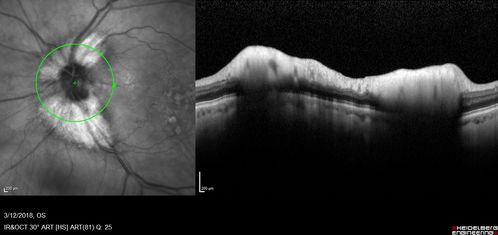

Myelinated Nerve Fiber Layer - Optic Nerve

Right eye subtle and inferior - left eye obvious